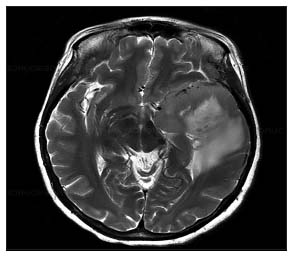

| Figure 2 Magnetic resonance imaging of diffuse astrocytoma Grade II